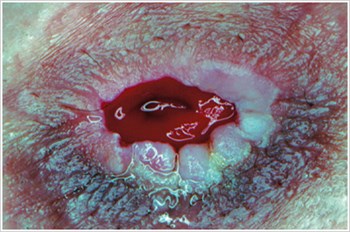

Piodermia gangrenosa

Descripción/causas:

Enfermedad inflamatoria de la piel que se observa a menudo en pacientes con enfermedad inflamatoria intestinal (EII), como la enfermedad de Crohn o la colitis ulcerosa.

Síntomas:

- Úlceras rojas infectadas, dolorosas, de forma irregular, con bordes enrollados de color rojo a púrpura; Aparecen en piernas, glúteos, cara y zona periestomal.